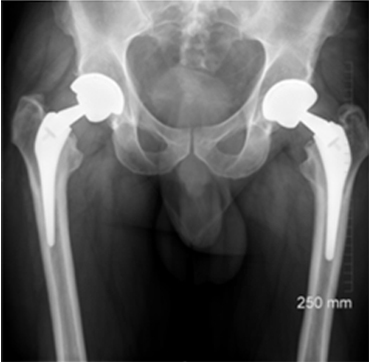

A middle-aged patient came to the clinic with severe pain and limited mobility in his left hip. Previously, he had undergone bilateral hip replacements that included modular necked femoral stems with ceramic-on-ceramic (CoC) bearings. However, the modular design led to corrosion between the titanium femoral stem and the cobalt-chromium neck, causing metal debris and an adverse tissue reaction in his left hip.

The challenge was in addressing the corrosion-related inflammation without exacerbating the damage to the surrounding bone, as the femoral stem was well fixed. Unlike cases with pseudotumors, the patient’s problem originated from metal debris due to the interaction of different alloys in the modular components.

Imaging studies confirmed the presence of metal debris and inflammation around the implant, particularly affecting the left hip. Despite the ceramic-on-ceramic bearing being intact, the corrosion at the modular junction between the neck and the stem was the main culprit. The diagnosis was an adverse reaction to metal debris, secondary to modular neck corrosion.

The surgery was successful, and at his six-week follow-up, the patient reported pain-free mobility and had resumed his daily activities. Imaging showed that the new primary stem had successfully integrated with the bone. At the two-year follow-up, the patient had a well-functioning hip, with no complications and clear evidence of bone growth around the implant, confirming the efficacy of the surgical approach.

This case represents ALTR with CoC. ALTR was characterized by tissue inflammation and extensive fluid accumulation around the ceramic implants. However, ALTR was not caused by the ceramic implant but by corrosion, which occurred between the titanium femoral stem and the cobalt-chromium neck.